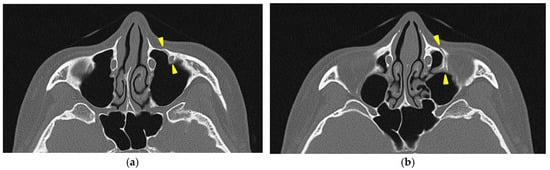

A separation of approximately 4 mm was observed in the midpalatal suture.

A head CT was performed on the same day. The axial slices revealed a 4 mm wide separation of the midpalatal suture (Figure 3). A fracture of the left maxilla was also observed. The line of this fracture extended from the orbital floor and the anterior surface of the maxilla (Figure 4), starting at the medial edge of the orbital rim, passing through the entire wall of the infraorbital foramen (Figure 5a,b), and reaching the maxilla’s alveolar process.

Figure 3. The axial view of the facial bone computed tomography at the level of the palatine bone. A separation of approximately 4 mm was observed in the area between the two yellow triangles in the midpalatal suture.